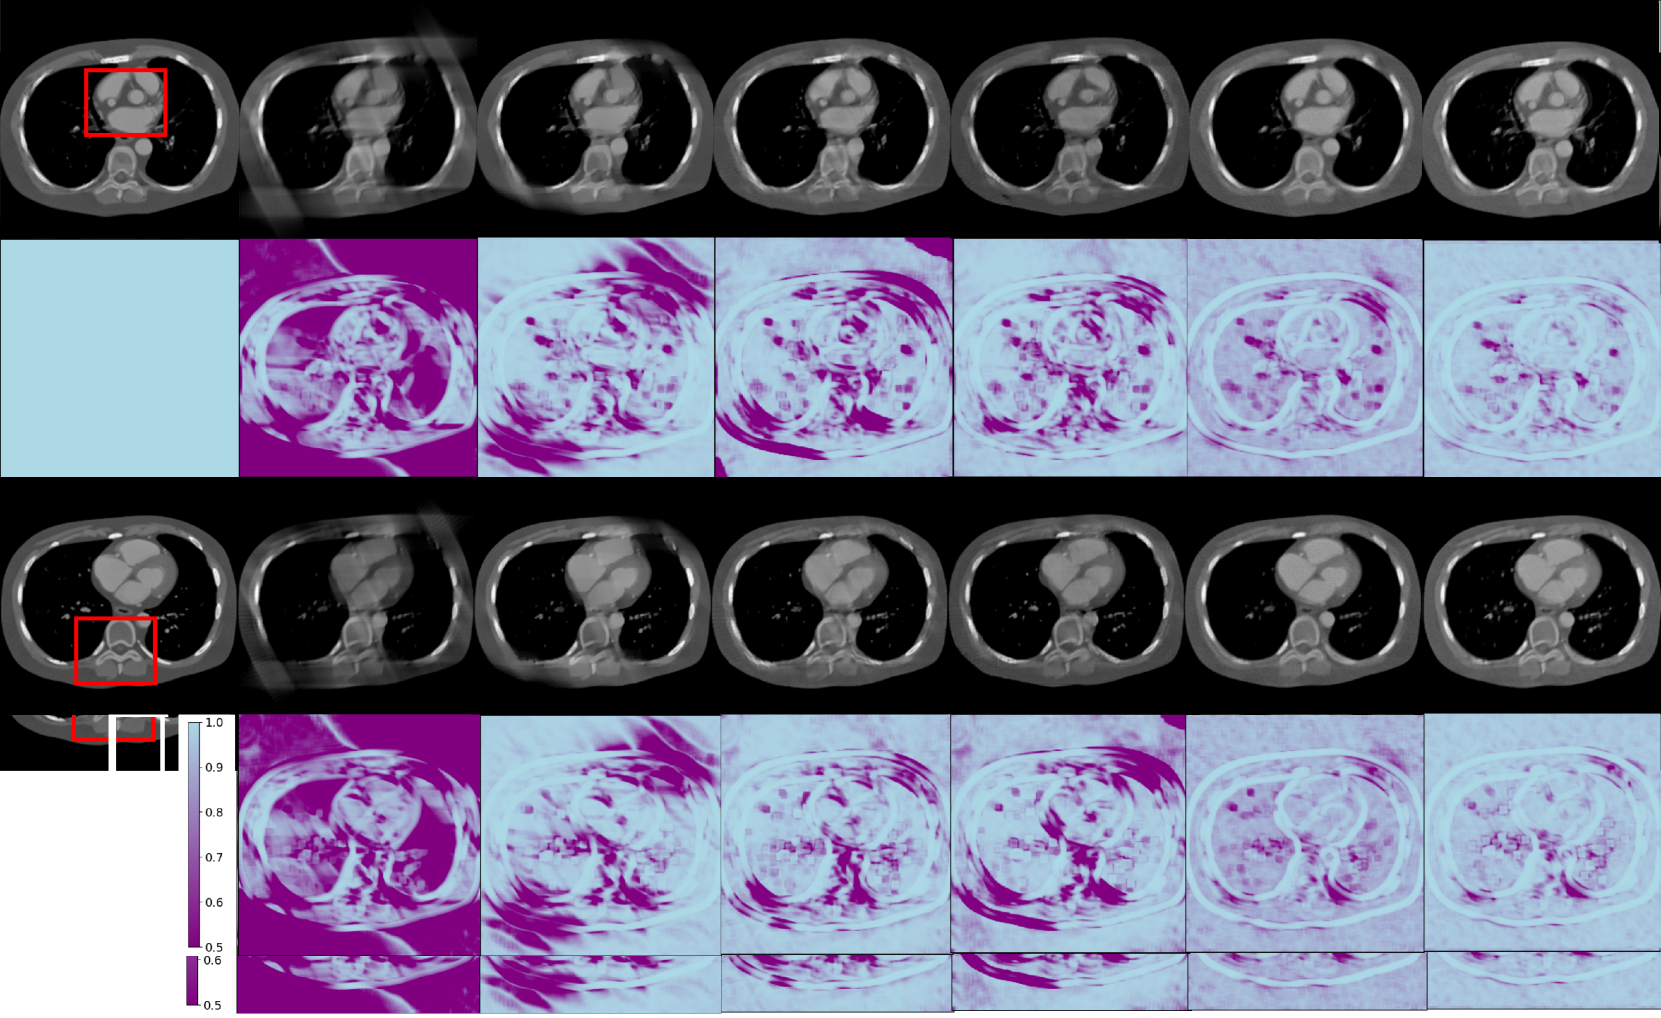

Refer to caption

Figure 2: Reconstruction results from the simulated dataset for different methods with a scanning angular range of 120° with Case 1 and Case 2. The 2ndsuperscript2𝑛𝑑2^{nd}2 start_POSTSUPERSCRIPT italic_n italic_d end_POSTSUPERSCRIPT and 4thsuperscript4𝑡4^{th}4 start_POSTSUPERSCRIPT italic_t italic_h end_POSTSUPERSCRIPT rows show the SSIM map compared to the ground truths. The display window is [540540-540- 540 1000100010001000] HU.

Fig. 2 shows the representative reconstruction results for patient 153 across phases 100 and 112, utilizing different methods for 120-degree limited-angle reconstruction. The first and third rows display the reconstruction results, while the second and fourth rows provide the corresponding SSIM map for comparative analysis. For the 120-degree condition, most of the methods achieve satisfactory results, except for FBP and PDHG-TV, which are affected by strong limited-angle artifacts.

FBPConvNet and TomoGAN show compromised edge quality along oblique directions, while the Diffusion-MBIR and PSDM demonstrate superior edge preservation. However, the Diffusion-MBIR images lack the finer details that are perceivable in PSDM images.

For further comparison, two regions of interest (ROIs) are extracted from Cases 1 and Case 2, and subsequently magnified as in Fig. 3. Upon close examination of the structures, specifically those indicated by the red arrows, it is evident that the images are subject to blur and distortion when they are processed by PDHG-TV, FBPConvNet, and TomoGAN. Conversely, the Diffusion-MBIR and PSDM yield superior image quality. However, it should be noted that Diffusion-MBIR images are not entirely devoid of imperfections, as they continue to retain some noise and exhibit minor distortions at the locations indicated by the red arrows. Furthermore, when looking closely at the area indicated by the red circles, PSDM provides clearer reconstruction of the LAD branches compared to Diffusion-MBIR.